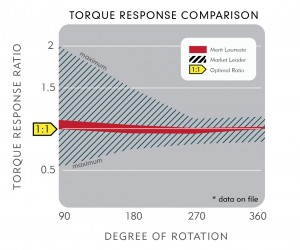

Designed to provide true 1:1 torque response to facilitate navigation and rapid vessel selection.

Comparative torque testing showed the Merit Laureate guide wire consistently met the 1:1 torque target.